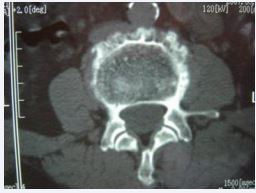

Figure 3 L4 Brucellosis spondylitis. CT shows new osteophyte at the edge of the vertebral body and the destruction focus in between constitutes the characteristic performance of “lace vertebrae”.

In 13 patients (18.57%), the bone at the edge of the vertebral body was stiffened like a bird’s beak, which was connected with the edge of adjacent vertebral body hyperplasia to form a bone bridge, and 11 patients (15.71%) had poor lumbar stability. CT showed 53 cases (75.71%) patients with vertebral edge disease have size about 2~6 mm multiple focal bone destruction, bone destruction around focal sclerosis of bone hyperplasia, bone of new born stove and new bone broken, the whole edge vertebral bodies like lace structure formation “lace vertebral (Figure 3)”; In 17 cases (24.28%), intervertebral disc lesions showed isodense shadows, articular cartilage surface sclerosis and hyperplasia, proliferated bony protruding toward the edge of the vertebral body to form “lip”-shaped osteophytes, anterior longitudinal ligament and paravertebral sides were calcified, and there were osteophytes connect (Figure 4); In this group, 18 patients (25.71%) had widened paravertebral muscles with abscess formation and clear surrounding space, but no abscess drainage imaging (Figure 5).

Imaging examination Early X-ray films only showed lumbar degeneration and vertebral osteoporosis, no spinal infection, and generally changed after 6 to 8 weeks of onset. Once X-ray signs appeared, they developed rapidly, and the vertebral body Marginal bone destruction and intervertebral space stenosis mainly, bone destruction concentrated on the upper or lower edge of the vertebral body, manifested as progressive intervertebral space stenosis, involving two adjacent vertebral bodies, and may be accompanied by destruction of intervertebral facet joints Caused spinal instability, but no vertebral body compression or wedge-shaped deformation, bone bridge was shown in the later stage, extremely sclerotic, but rarely bony fusion, 53 cases in this group showed narrow intervertebral space, vertebral edge bone destruction, 17 cases of vertebral body Marginal bone hyperplasia forms a bone bridge; CT examination can clearly show the degree of bone destruction in the lesion, whether there is a cavity and paravertebral abscess formation, the intervertebral disc is destroyed as an isodensity shadow, the pedicle is not destroyed, and the periosteum at the edge of the vertebral body is hypertrophic and calcified due to inflammation stimulation, forming a “lip-like” Osteophytes, new bone at the edge of the vertebral body interlaced with small destructive foci to form “lace vertebrae”, “lip-shaped” osteophytes and “lace vertebrae” constitute the characteristic manifestations of BS, and CT is unique in showing paravertebral abscesses around the lesion.

The advantages of CT-guided puncture abscess and biopsy are also available. In this group, 53 cases had the characteristic manifestation of “lace vertebrae” and 17 cases formed “lipshaped” osteophytes, and 18 cases showed paravertebral abscesses; The main value of MRI examination is to display abnormal signals at the stage of inflammatory infiltration, to determine the involvement of the spine and the scope of lesions, and to clearly show vertebral osteomyelitis, intervertebral disc destruction, paravertebral abscess, and intraspinal epidural abscess. Damaged intervertebral disc or inflammatory granulation tissue protrudes into the vertebral canal, causing compression of the corresponding plane dural sac [2,7,8]. MRI can guide surgical treatment, 44 cases of this group MRI showed dural sac or nerve root compression. Pathological manifestations include histiocytosis and non-tuberculous granuloma formation. Microscopically, infiltration of neutrophils, monocytes, lymphocytes, and eosinophils was observed, and proliferative nodules composed of patches of epithelioid cells were visible. In this group of 42 patients, pathological examination was performed on all lesions removed during surgical treatment, which conformed to the histological findings of brucellosis [1,7].